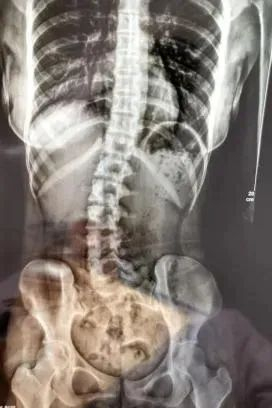

做过x光检查后

医生发现小邹腰椎向右侧弯、旋转

明显侧弯

▲小邹的脊柱明显侧弯